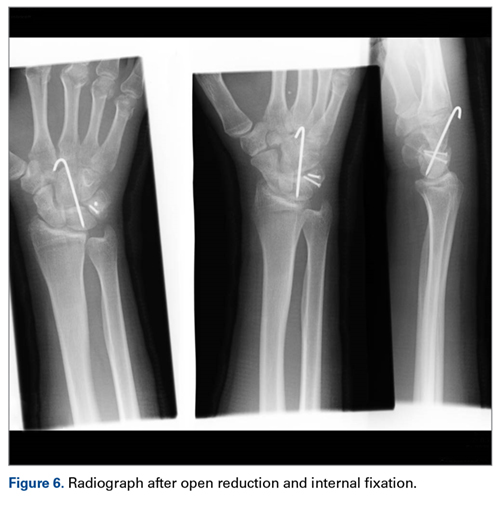

Later, however, the hand surgery team evaluated the radiograph as well as computed tomography (CT) scans and found a translunate, transradial, transtriquetral, transtrapezoid perilunate dislocation of the wrist with multiple metacarpal neck fractures ( Figures 1-5 ).The next day, with the patient under general anesthesia, an attempt to reduce the perilunate dislocation by manipulation was unsuccessful. Open reduction and internal fixation (ORIF) were performed through a dorsal approach; the perilunate dislocation was reduced and stabilized with lunocapitate 1.2-mm Kirschner wire (K-wire). The scapholunate and lunotriquetral ligaments were found to be intact, and the significantly displaced triquetral fracture was treated with internal fixation involving 2 minifragment screws ( Figure 6 ).

The other carpal fractures were nondisplaced and fixation was not required. The wrist was immobilized in a full cast. At 4 weeks, K-wire and cast were removed and the wrist mobilized under supervision of a hand therapist. Satisfactory radiologic union was noted at 6 weeks. Further follow-up was arranged at 3 months, 6 months, and 1 year ( Figure 7 ). At 6 months, the patient had full range of motion and good grip strength. At 12 months, the outcome was excellent (Mayo Wrist Score = 90).Discussion

The goal in the treatment of perilunate dislocation with multiple carpal fractures is anatomical reduction and restoration of carpal alignment—which frequently require ORIF, though acute salvage procedures like proximal row carpectomy may be considered in irreparable fractures with extensive ligament injuries. 9 For open reduction, the approach can be dorsal, volar, or a combination. The approach in our patient’s case was dorsal. His triquetral fracture, his only displaced fracture, was treated with internal fixation. All other fractures were nondisplaced, stable, and did not warrant internal fixation.